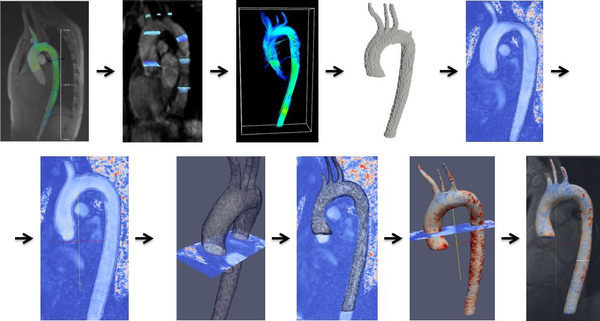

1.4.1.1 4D flow cardiovascular magnetic resonance imaging

At present, 4D flow cardiovascular magnetic resonance imaging (4D CMRI) sequences are being a promising tool to visualize and quantify 4D (3D+t) blood flow. From these sequences the raw data can be obtained and conveniently processed, allowing visualization of the blood flow patterns in any segment of the cardiovascular tree[71][72][73]. Nevertheless, the visualization of these images entails an important manual work, becoming a very time-dependent task and then turning out to be not useful in the current clinical practice. Therefore, it is important to improve the technology and the methods of automatic representation of the 4D blood flows, in particular for the WSS analysis. In chapter 5, it is demonstrated that 4D flow CMRI technique is a reliable tool to provide the boundary conditions for the Computational Fluid Dynamics(CFD) in order to estimate the WSS within the entire thoracic aorta in a short computation time. Our image-based CFD methodology exploits the morphological MRI for geometry modelling and 4D flow CMRI for setting the boundary conditions for the fluid dynamics modelling. The aim is to evaluate visualization of well-defined aortic blood flow features and the associated wall shear stress by the combination of both techniques. In that sense, CIMNE has developed a home-made ad-hoc software (Aorta4D) oriented to make progress in this field of work [72][74][73]. Aorta4D will afford analysis and spatially visualization of the registered 3-directional blood flow velocities, and perform a 3D semi-automatic segmentation based on the 4D flow CMRI data.

Contribution to the paper: This work is being carried out in collaboration with the E.T.S. d'Enginyeries Industrial i Aeronáutica de Terrassa (ETSEIAT), UPC and the Unidad de Imagen Cardiaca, Servicio de Cardiología, Hospital de la Santa Creu i Sant Pau. The simulation in the OPENFOAM software([88]) was performed during the final career project of Jordi Casacuberta in the ETSEIAT. The author of this monograph has developed the algorithm and the methodology for the calculation of the WSS using 4D flow CMR data in collaboration with Jorge S.Pérez (CIMNE). The author of this monograph has also contributed in the segmentation and the analysis of results.

Two new collaborations with the Hospital Sant Pau i Creu Blanca, Barcelona, Spain are now beginning. Both are related with the 4D flow CMR acquisition, Aortic Dissection and Portal pressure. Related to the Aortic Dissection, the objective is to improve the clinical intervention procedure, we are going to combine 4D flow CMR sequences with CFD to estimate the relative pressure in the true and false lumen. And related to the Portal pressure, the goal is to use 4D flow CMR sequence to estimate the flow and pressure in the Portal system with the objective of check the liver function. Besides of the clinical applications, a prototype of the software (AORTA4D) to visualize and quantify 4D flow CMR data is currently being developed in collaboration with GiD Department of CIMNE.

|

| Figure 15: Preliminary concept of automatic segmentation of the Aorta based on 4D MRI data |